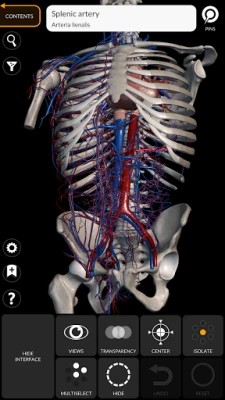

"Anatomy 3D Atlas" allows you to study human anatomy in an easy and interactive way.

Through a simple and intuitive interface it is possible to observe every anatomical structure from any angle.

The anatomical 3D models are particularly detailed and with textures up to 4k resolution.

The subdivision by regions and the predefined views facilitate the observation and the study of single parts or groups of systems and the relationships between different organs.

ANATOMICAL 3D MODELS

• Cardiovascular system

• Simple and intuitive interface

• Rotate and zoom each model in 3D space

• Option to hide or isolate single or multiple selected models

• Filter to hide or display each system

• Transparency function

• By selecting a model or a pin, the related anatomical term shows up

"Anatomy 3D Atlas" allows you to study human anatomy in an easy and interactive way.

Through a simple and intuitive interface it is possible to observe every anatomical structure from any angle.

The anatomical 3D models are particularly detailed and with textures up to 4k resolution.

The subdivision by regions and the predefined views facilitate the observation and the study of single parts or groups of systems and the relationships between different organs.

• Simple and intuitive interface

• Rotate and zoom each model in 3D space

• Option to hide or isolate single or multiple selected models

• Filter to hide or display each system

• Transparency function

• By selecting a model or a pin, the related anatomical term shows up